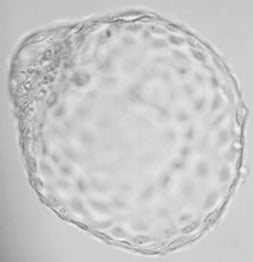

7. We also have world-leading success with Day 5 blastocyst transfers. Growing an embryo and its subsequent transfer at the blastocyst stage allow selection of the best quality embryos with an expected good viability – it is reliability predicted by extended culture. (read more about extended culture)